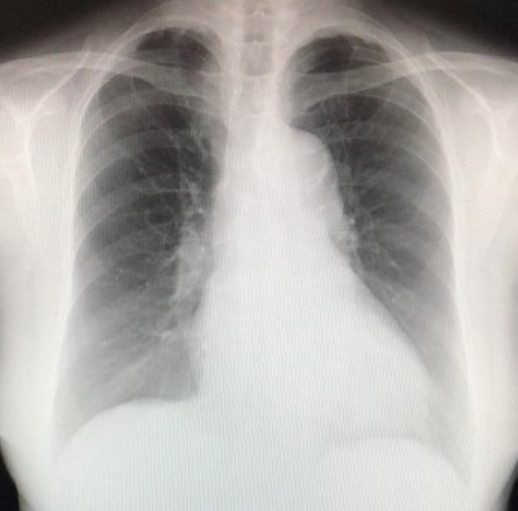

入院後治療と経過

①呼吸が困難であったため、マスク式呼吸補助装置(BIPAP)を装着

②薬剤投与:強心剤、利尿剤、血管拡張剤など

③治療の効果

・体重の減少:浮腫の軽減により入院時よりも20kg超減少

・血液検査の改善

NT-PROBNP(心不全の指標):19806(入院時) ⇒ 192 pg/ml(正常<125)

肝・腎機能:正常化

④入院期間35 日にて退院。

退院後1年8カ月の現在外来通院中。経過良好。

胸部単純X線像